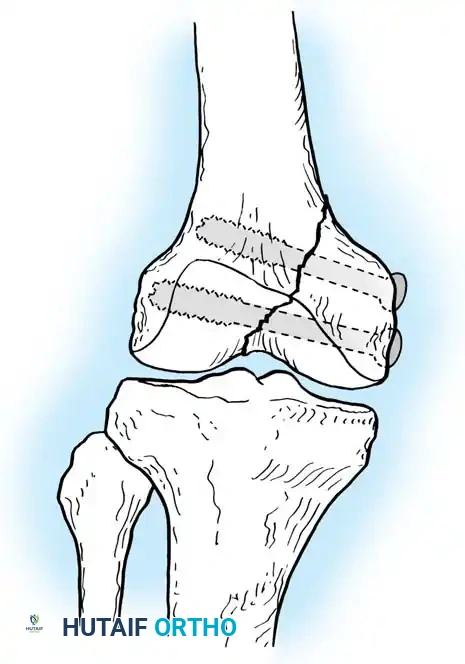

Osteochondral fractures of the knee represent a distinct clinical entity that frequently results in the formation of intra-articular loose bodies. Historically, an extensive survey conducted by the Army Air Force of approximately 186 patients with loose bodies in the knee revealed that in 21 of these cases, the loose bodies were the direct result of osteochondral fractures originating from either the femur or the patella. Subsequent literature by Rosenberg, Ahstrom, Kennedy, Grainger, and McGraw has corroborated these findings, establishing a clear pathoanatomical pattern.

Rosenberg specifically identified that osteochondral fractures of the lateral femoral condyle are disproportionately common in adolescent boys. The primary biomechanical mechanism is often a transient lateral dislocation of the patella. As the patella relocates, it shears off a fragment of the lateral femoral condyle. Because these fragments possess a strong tendency to migrate and cause mechanical symptoms (locking, catching, and accelerated chondrolysis), surgical intervention is almost universally required.